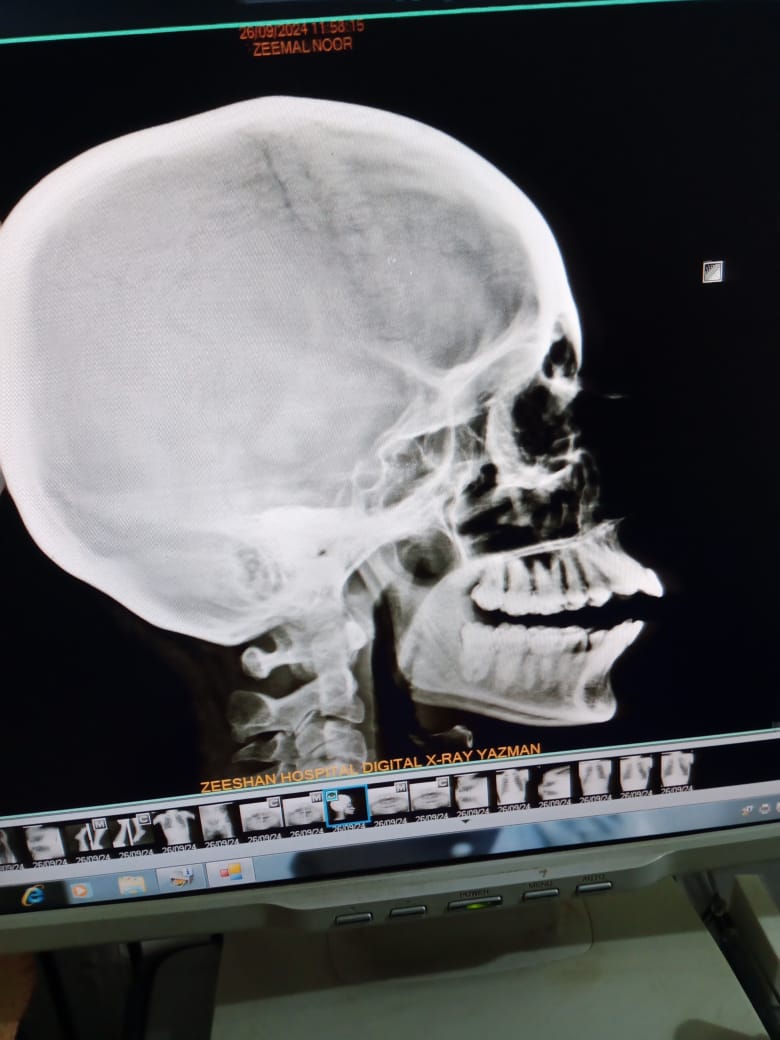

I have a misalignment with my teeth being a bit forward. Could you please provide information on the cost of aligners and braces? Also, which option would be more suitable for correcting this issue?

I think your case is surgical orthognathical case .needs ceph analysis visit your nearest dental hospital